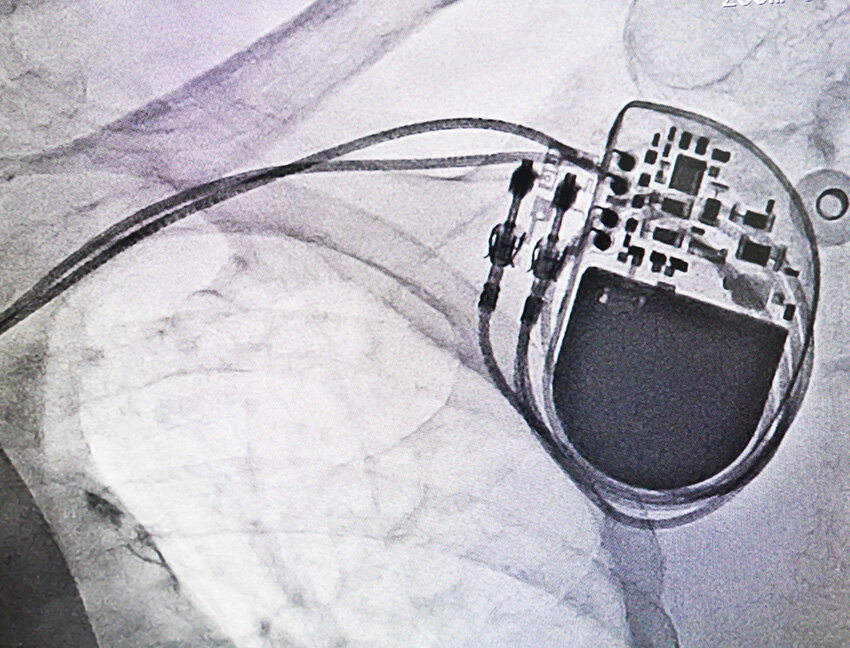

Image of a pacemaker device insertion.